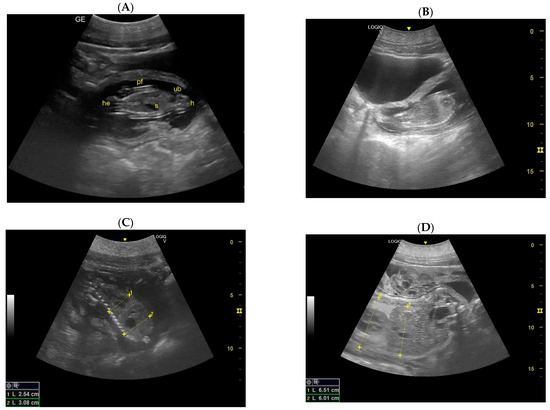

- Day 113 ± 4 post-ovulation: The embryonic vesicle was first recognizable in the uterine cavity as a roundish structure with an average diameter of 1.71 cm with an anechoic content. In addition, it is possible to recognize the embryo inside it as an elongated hyperechoic structure (Figure 2). Thanks to these findings, it has been possible to make a diagnosis of pregnancy.

- Day 162 ± 2 and 170 ± 2: Skeletal formations, such as the cranial bone, vertebrae, costal bones, limbs, and detailed regions such as fingers, were first observed. The first abdominal organs to be visualized are the stomach and the urinary bladder, which appear as distinct and anechoic cavities. At the same time, it was possible to observe fetal movements.

- Day 186 ± 2: It is possible to identify the heart, lungs in the thorax, diaphragm in the middle, and liver and stomach in the abdomen. (D) Lungs appear as hyperechoic structures on the sides of the heart, and the latter seems to have a similar echogenicity compared to the liver (Figure 4).

- Day 197: The umbilical cord is already seen like a hyperechoic cord form structure; it is important to identify the course, and to evaluate the internal vascular components and the absence of knots or torsions until the birth (Figure 5).